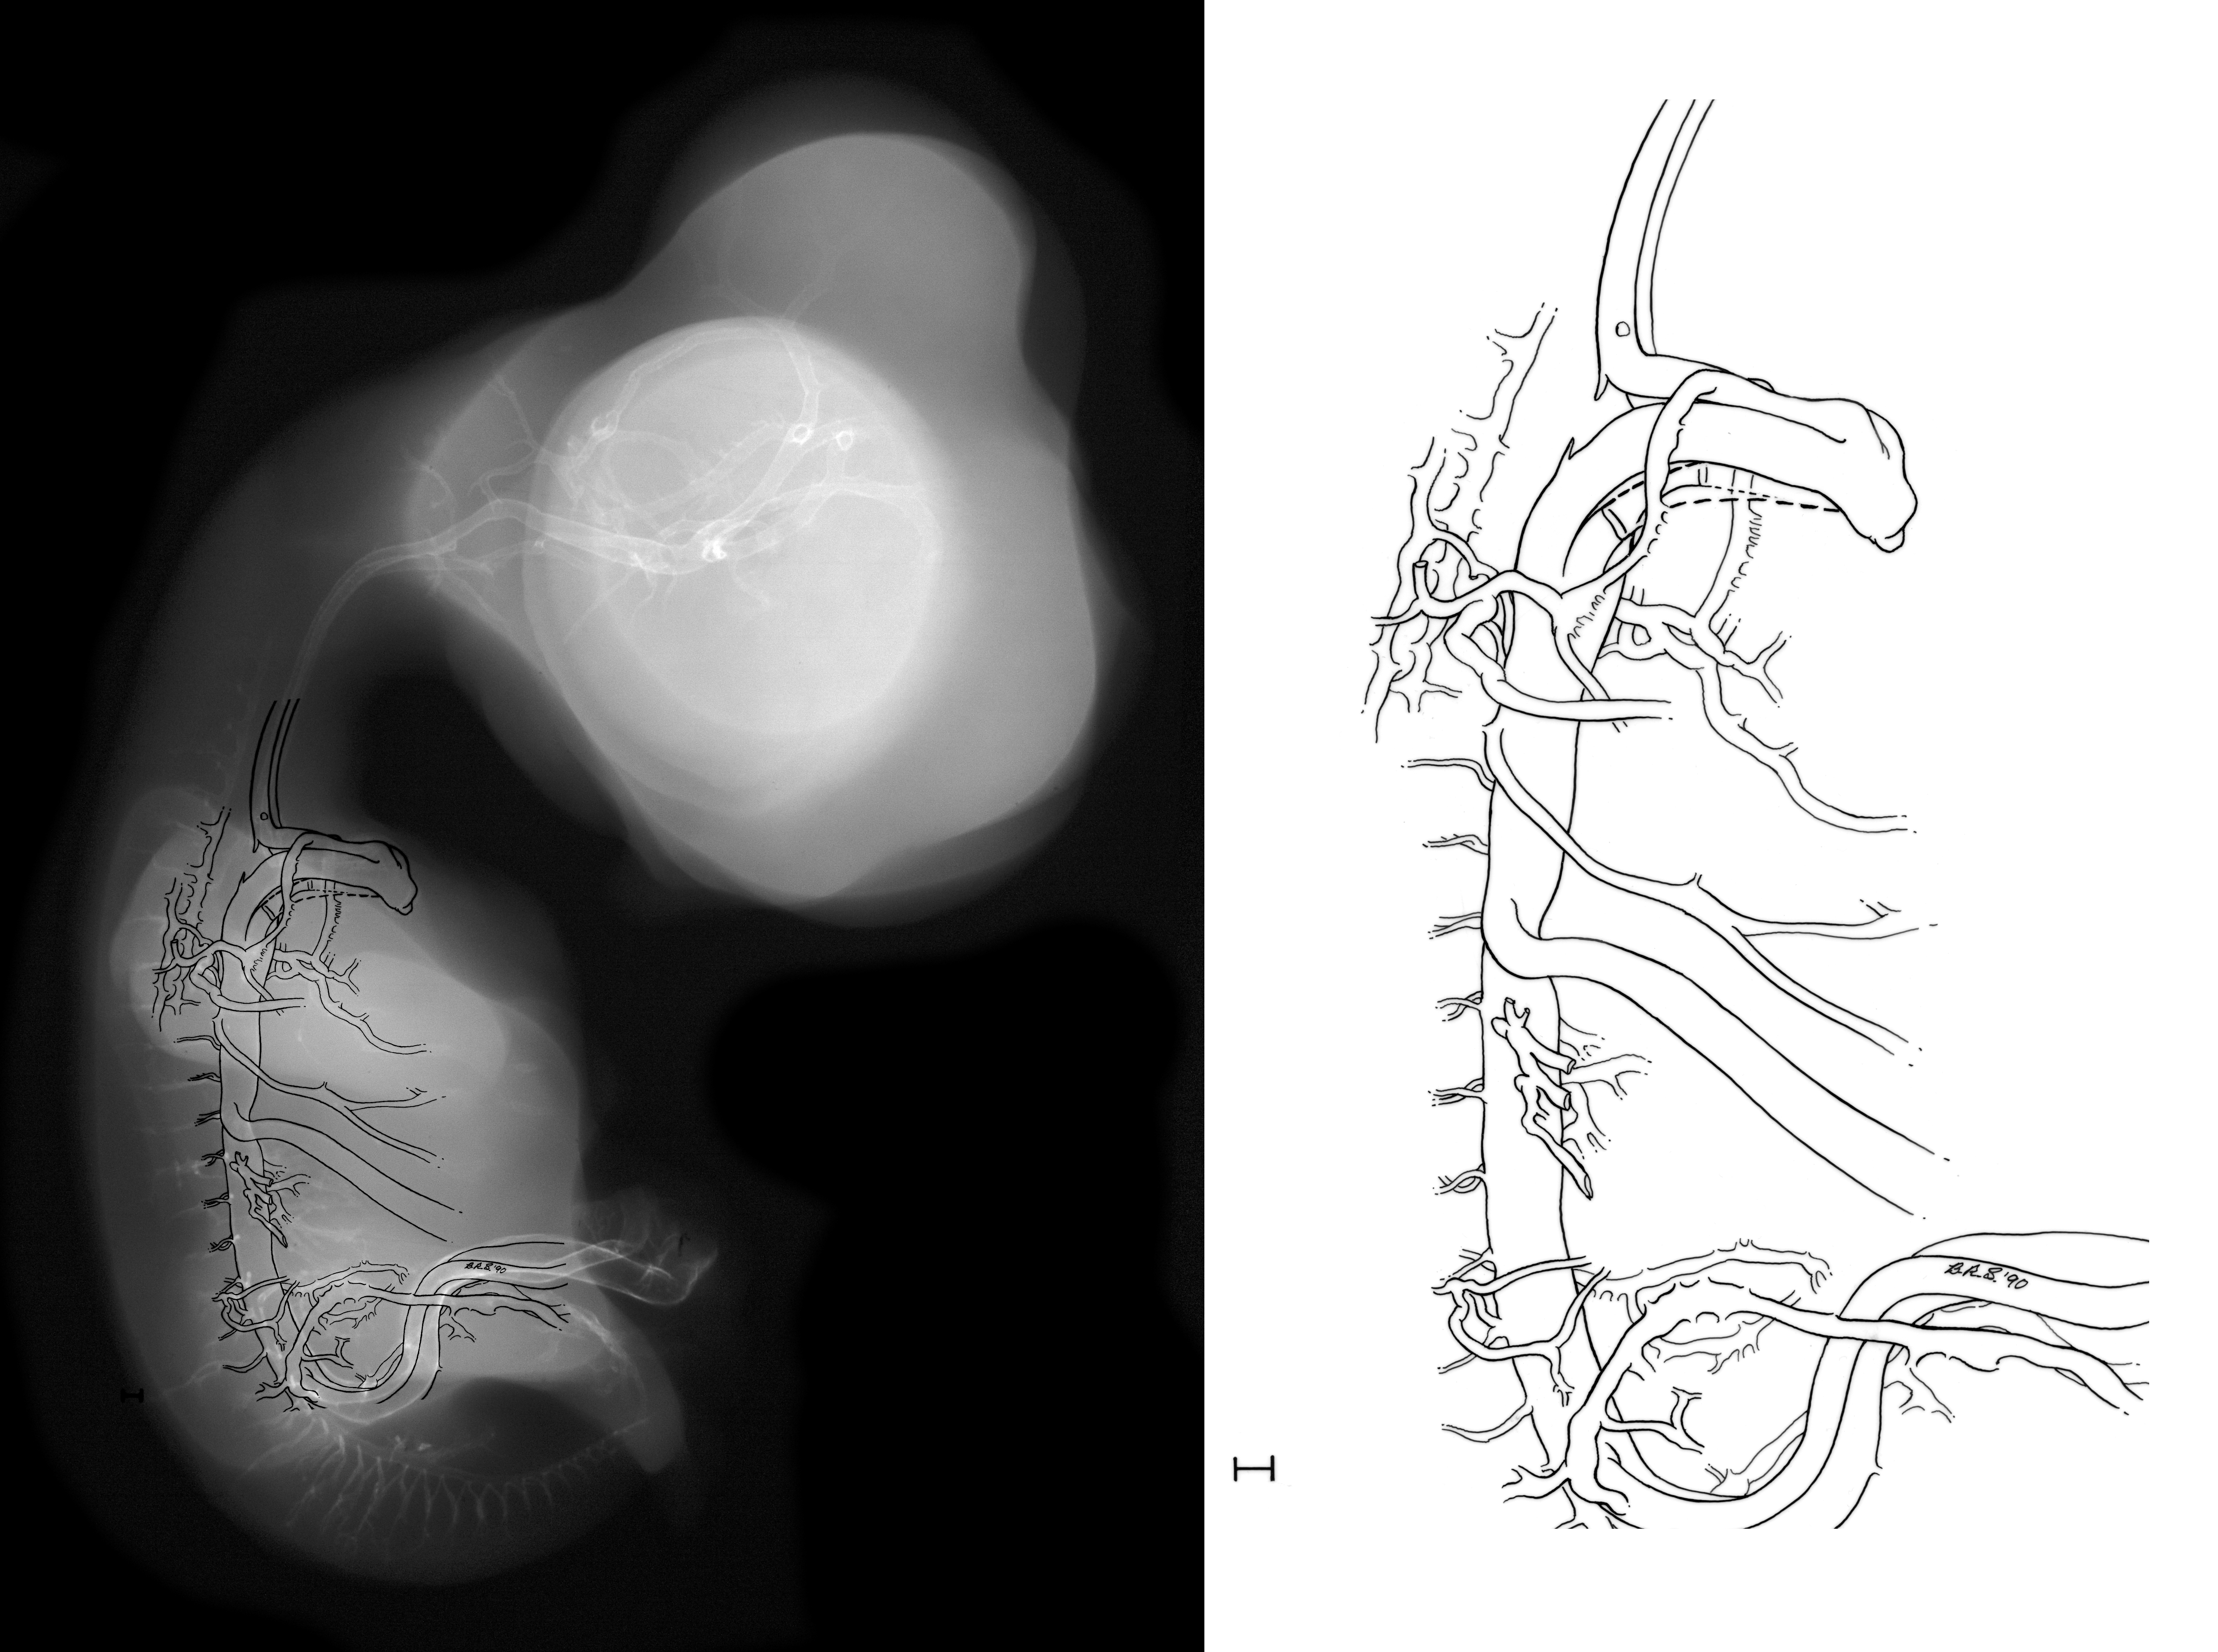

Chick Embryo Microangiography

Hamburger-Hamilton (HH) Stage 30 (approx. 6.5 days)

Stereo X-Ray Micrographs

Drawing